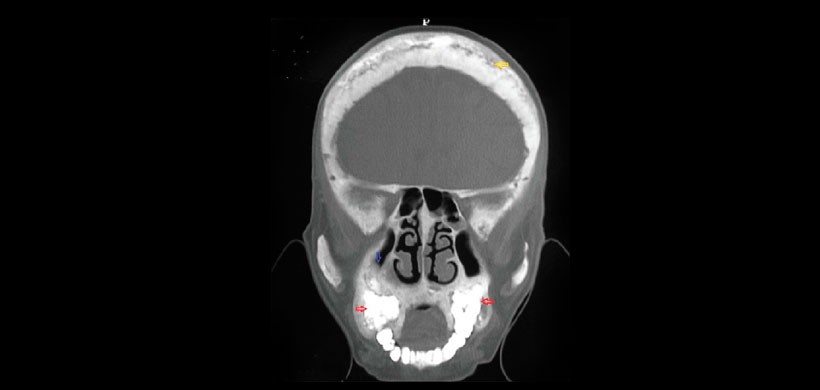

Fig 3. Vista coronal de la tomografía computarizada en la que se zonas escleróticas y lesiones líticos en la bóveda craneal ósea que dan una apariencia de copos algodón (flecha amarilla) con obliteración del seno maxilar a la derecho.